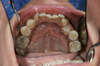

APRES